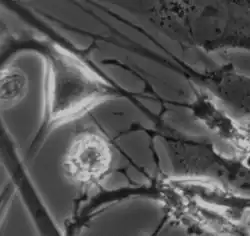

The myenteric plexus from the rabbit. X 50.